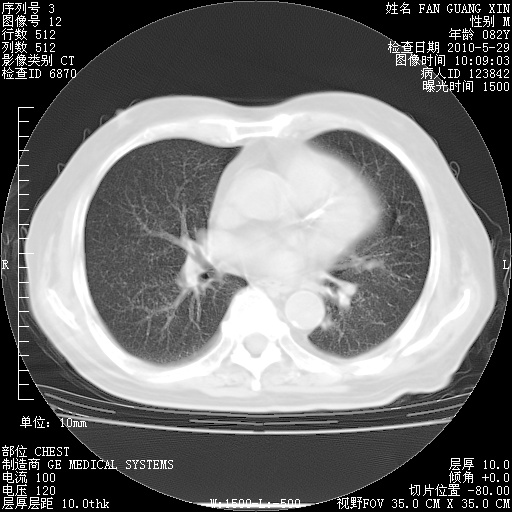

再治疗10天后的肺部CT

再治疗10天后的肺部CT 纵膈窗

从白细胞总数和中性比例看好像合并感染。肺部纹理好像比上次多,支气管炎?其他感染?

阅读此次胸部CT,肺间质渗出性改变较入院时有吸收。目前从体温、白细胞、中性分叶明显增高,肯定存在细菌感染(发生医院感染哦,若无消化道及泌尿系统等感染的依据,肺部感染可能大)。若你院头孢哌酮舒巴坦钠耐药率较高,同意你的方案,若48小时体温仍高,可考虑使用碳青霉稀类抗菌药物,同时可予超声雾化、注意滴数时加大液体量。白蛋白33.30g/L较低哦,需加强营养等支持治疗。